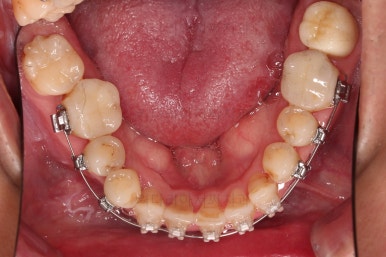

1. 초진 시 입안의 모습

부산구순구개열교정 키다리아저씨치과에 처음 내원하셨을 당시의 입안의 모습입니다.

이번 환자분도 이와 같은 일반적인 특징이 그대로 나타나 있었습니다.

양측성 구순구개열이었으므로 작은 앞니(대문니와 송곳니 사이)가 양쪽 다 결손이었고, 또 다른 이유로 아래 앞니도 1개 없는 상태였습니다.

위아래 장치를 부착했습니다.

초기 단계의 주안점은 아랫니와 악궁과 어울리는 윗니 악궁의 형태를 만들어 주는 것이고요.

악궁확장장치를 사용하지 않은만큼 철사의 형태를 잘 잡아가면서 악궁 형태를 개선시킵니다.